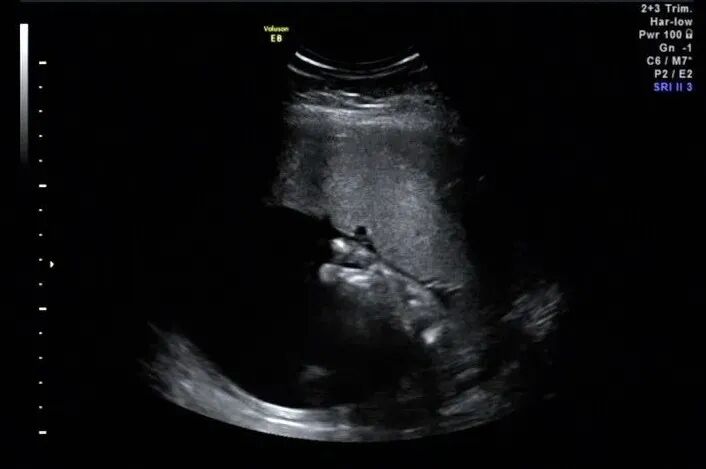

手指横断面仅显示两个,指间隙明显增大,裂隙深

再看脚也不对劲,马上启动三维超声,下图是三维超声表现